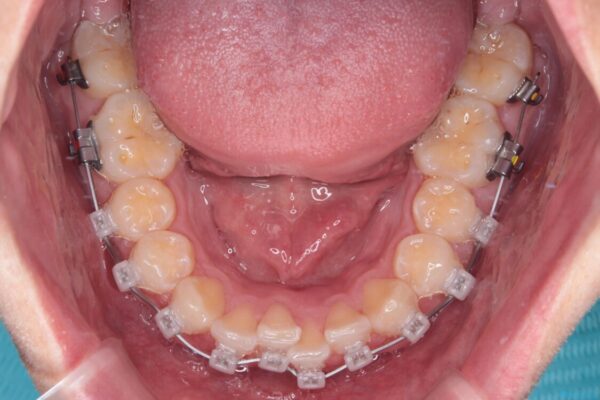

・費用と期間を抑えるために、多少目立っても効率の良いメタルブラケットを使用

・奥歯のシザーズバイト改善には、口蓋側にアンカースクリュー(TAD)を設置し、矯正用ゴムで内側に牽引

・捻転した第二小臼歯は、ワイヤーと矯正用ゴムの力を用いて正しい位置へ回転移動

治療途中

• 前歯のガタガタ・奥歯のかみ合わせ(シザーズバイト)を改善|1年半で完了したメタルブラケット矯正 治療途中画像